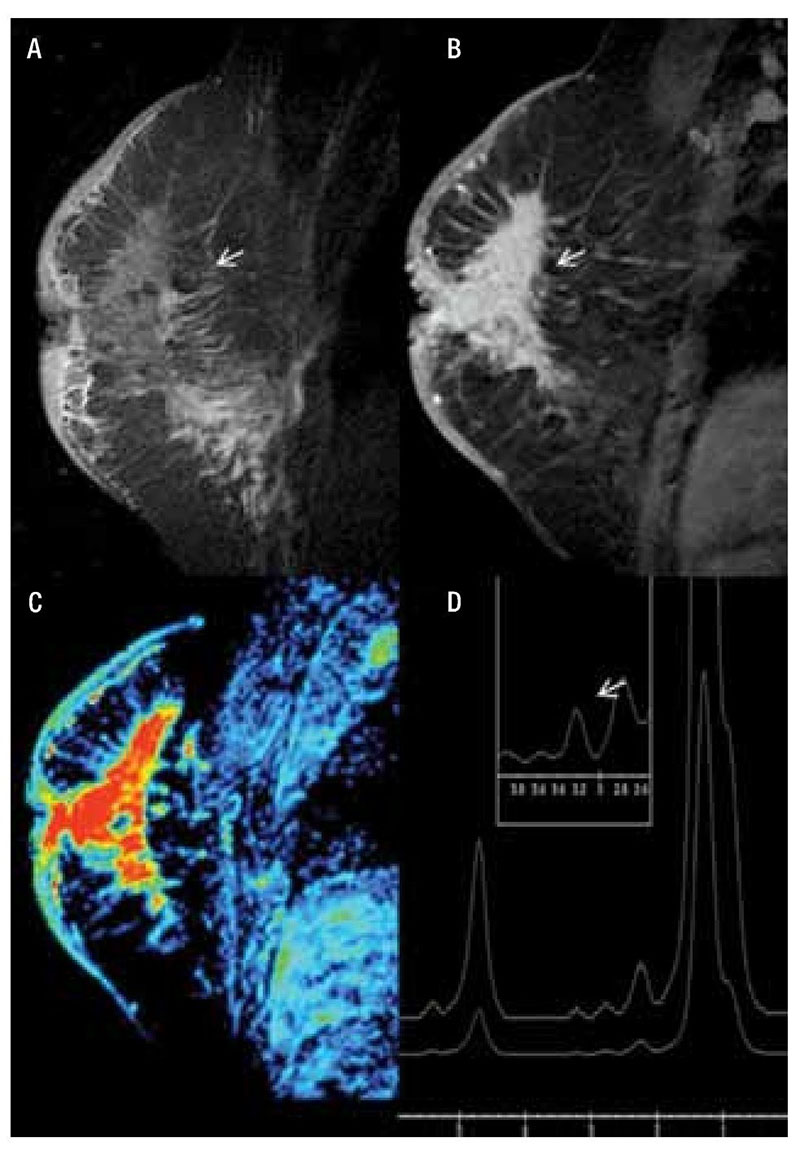

La estimulación magnética pulsada se aplica de manera no invasiva (externa) en zonas particulares del cuerpo o de manera general, lo cual permite la inducción de microcorrientes eléctricas en el tejido que se estimula. Dichas microcorrientes a su vez desencadenan una serie de efectos que como se han descrito a lo largo de estos newsletters mensuales, permiten aplicar la estimulación magnética en una gran gama de enfermedades. Sin embargo, para el caso de cáncer, resulta de vital importancia la localización del pulso magnético, ya que esto propicia que haya un efecto dirigido a un sitio en particular y así reducir los efectos adversos derivados por otro tipo de terapias (tales como la quimioterapía). De este modo, existen en las plataformas de literatura científica, cerca de 4000 estudios distintos que evalúan los efectos de la estimulación magnética en modelos in vitro, in vivo y en ser humano para diferentes tipos de cáncer. Una de las investigaciones más importantes es la que realizaron Crocetti y sus colaboradores en 2013 [12]. En este estudio, se evaluó el efecto de selectividad de la estimulación magnética pulsada (PEMF) para matar células con cáncer de mama. Para tal propósito, los investigadores utilizaron un cultivo celular de cáncer de mama (MCF7) y un cultivo con el mismo tejido, pero sano (MCF10). Ambos tipos de células fueron expuestas a la estimulación PEMF a diferentes frecuencias (entre 20 y 50 Hz), intensidades (de 2 a 5 mT) y tiempos de estimulación (de 30 a 90 min) diario por 3 días consecutivos. Técnicas como el azul de tripano, ruptura de DNA para determinación de apotosis y citometría de flujo de impedancia fueron utilizadas para evaluar la viabilidad, cambios genéticos y propiedades eléctricas, respectivamente, en ambos cultivos. Los resultados expuestos en la figura 3, muestran que la terapia PEMF a 3mT de intensidad fue la que tuvo el mayor grado de letalidad únicamente en las células cancerígenas, ya que causo un incremento considerable en la muerte celular del cultivo MCF7 y un efecto nulo en las MCF10 (normales). Por otro lado, el tiempo de estimulación que tuvo un mayor efecto fue el de 60 minutos, ya que respecto a los 30 y 90 minutos fue el que mostró una mayor taza de mortalidad. Finalmente, de acuerdo con el reporte de los investigadores, la frecuencia de 20 Hz fue la única que tuvo un efecto en las células cancerígenas y ningún daño a las células normales, mientras que la frecuencia de 50 Hz, no causo ningún daño a ningún tipo de células.

Figura 3. Efecto de la terapia PEMF en cultivos celulares de cáncer de mama

A) La estimulación magnética y el ultrasonido son dos propuestas modernas para propiciar daños a las células cancerígenas de manera específica y no invasiva. Estas técnicas en combinación con los Sistemas de entrega de fármacos pueden ofrecer un efecto anticancerígeno considerable por distintos mecanismos celulares.

B) Los campos magnéticos pulsados se liberan a través de dispositivos especializados para y han sido probados a en ensayos in-vitro, in vivo y en estudios en humanos

Este estudio muestra los efectos de la exposición de células cancerígenas a PEMF con 3mT de intensidad, 20 Hz de frecuencia y por 60 minutos diarios por 3 días consecutivos. Las conclusiones resaltan el potencial anticancerígeno de la terapia PEMF y su selectividad para causar daño únicamente en las células cancerígenas y no en las células sanas. Sin duda alguna, esta información es de vital importancia para implementar los parámetros necesarios para el tratamiento de este tipo de cáncer en particular.